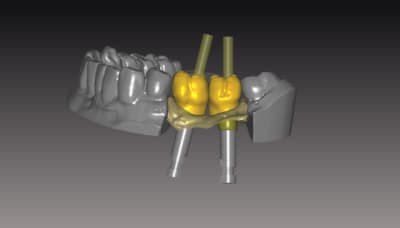

19/10/2011 à 19h42

le ptit dernier pour la route

IMPLANT NB REPLACE

nouveauté du system . 2 ccZR transvissées SOLIDARISEE sans base titan

sur des connections interne....

J insiste sur la possibilité et l'avantage de régler les profils d'émergences . de un, on epouse parfaitement la gencive sans trop la mal traiter , et de 2 l'aspect final des couronnes s'en ressent car on a beaucoup moins cet effet de cintrage au collet de la dent qui souvent donne des etrangetées morphologique .

Vous pouvez voir également le puit ( en occlusal)qui depasse de la structure et qui epouse la morpholgie de la ceramique à venir .. assez sympa et bien pratique pour vous lors du rebouchage avec le compo ...